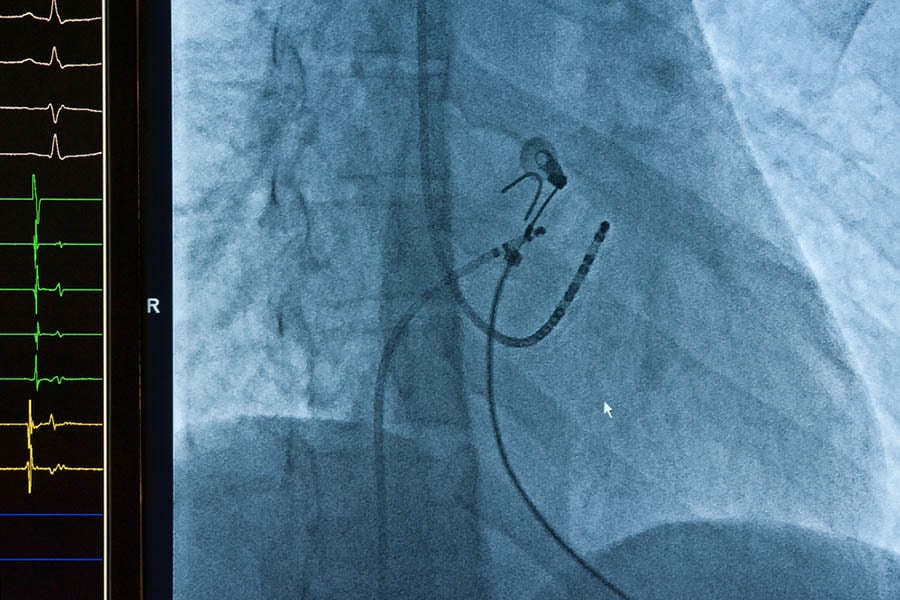

- Лекарят ще направи пункция, за да осигури достъп до вена или артерия в слабинната гънка, ръка, врат или бедро. След това в кръвоносния съд се въвежда интродюсер (въвеждаща тръбичка с диаметър, по-малък от този на пластмасова сламка). През него се въвежда катетър – гъвкава, дълга и тънка тръбичка. Позицията на катетъра се наблюдава в реално време на екран, което осигурява висока прецизност. Болка не се усеща, само дискомфорт.

- В зависимост от вида на аритмията и необходимата диагностика, през интродюсери се въвеждат няколко електродни катетъра – обикновено между два и пет. Всеки интродюсер осигурява стабилен достъп за отделен катетър. Катетрите служат за регистриране на електрическата активност на сърцето, а един от тях – за извършване на самата аблация.

- За да се установи къде се заражда аритмията, по един от електродните катетри се подава слаб електрически импулс, който стимулира сърдечната тъкан. Други електродни катетри регистрират електрическите сигнали на сърцето и така се определя зоната, отговорна за аритмията.

- След като лекарят установи къде се заражда аритмията, той насочва аблационния катетър към проблемната зона. В зависимост от случая, най-често се използва радиочестотна енергия (топлина) или криоенергия (студ). Чрез тази контролирана енергия се унищожават клетките, които карат сърцето да бие неравномерно, т. е. които причиняват аритмията. Процедурата обикновено е безболезнена, като пациентът може да усети само лек, краткотраен дискомфорт.